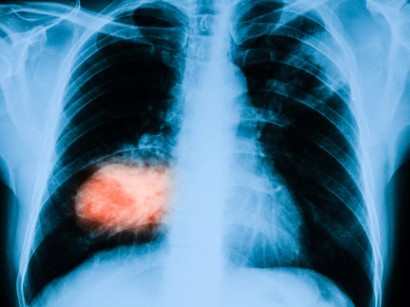

Neues Präparat bremst Knochenmetastasen Die Lebenserwartung von Krebspatienten mit Metastasen in den Knochen läßt sich mit Hilfe eines neuen Medikaments verdoppeln. In Deutschland ist bisher der Antikörper Denosumab zugelassen. Mit einem modernen Bisphosphonat das den Abbau von Knochengewebe bremst kann man diesen Komplikationen wirksam vorbeugen wie eine kürzlich publizierte Studie deutlich machte.

Radium-223-dichlorid wird eingesetzt um Absiedelungen von Prostatakrebs in Knochen zu behandeln die häufigste Form der Metastasen bei dieser Krebsart. Potenzielle Waffe gegen streuende Tumore. Seit Juli diesen Jahres ist der Wirkstoff in Deutschland auch zur Therapie bei Knochenmetastasen zugelassen.

Betroffene können am Klinikum rechts der Isar an einer klinischen Studie mit dem Präparat Alpharadin teilnehmen das in Vorstudien positive Effekte auf Knochenmetastasen und die Krebserkrankung erzielt hat. Forscher haben ein mögliches Mittel gegen die Metastasenbildung bei Krebs entdeckt. Die Hemmung des RANK-Ligand durch Denosumab unterdrückt die Knochenresorption und bremst so den Teufelskreis der Knochenzerstörung bei ossären Metastasen.

Vor allem in den Fällen in denen sich bereits Knochenmetastasen gebildet haben soll das radioaktive Präparat Schmerzen lindern und die Überlebenszeit verlängern. Von Ulrich Brunner Eschborn.